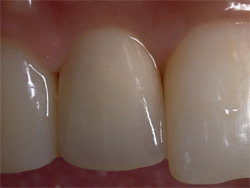

| インプラントの上のクラウンにより、あなたの咀嚼機能と自然な風貌が回復するでしょう。 |

| 数本のインプラントにより支えられるブリッジかクラウンにより、機能と顔立ちが回復するでしょう。 |